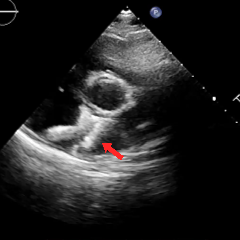

冠状动脉CTA:冠状动脉分布呈均衡型,左前降支中段浅肌桥;余冠状动脉CTA未见明显异常;卵圆孔未闭;左房囊袋。

冠脉CTA(长隧道+大开口+左房囊袋PFO)